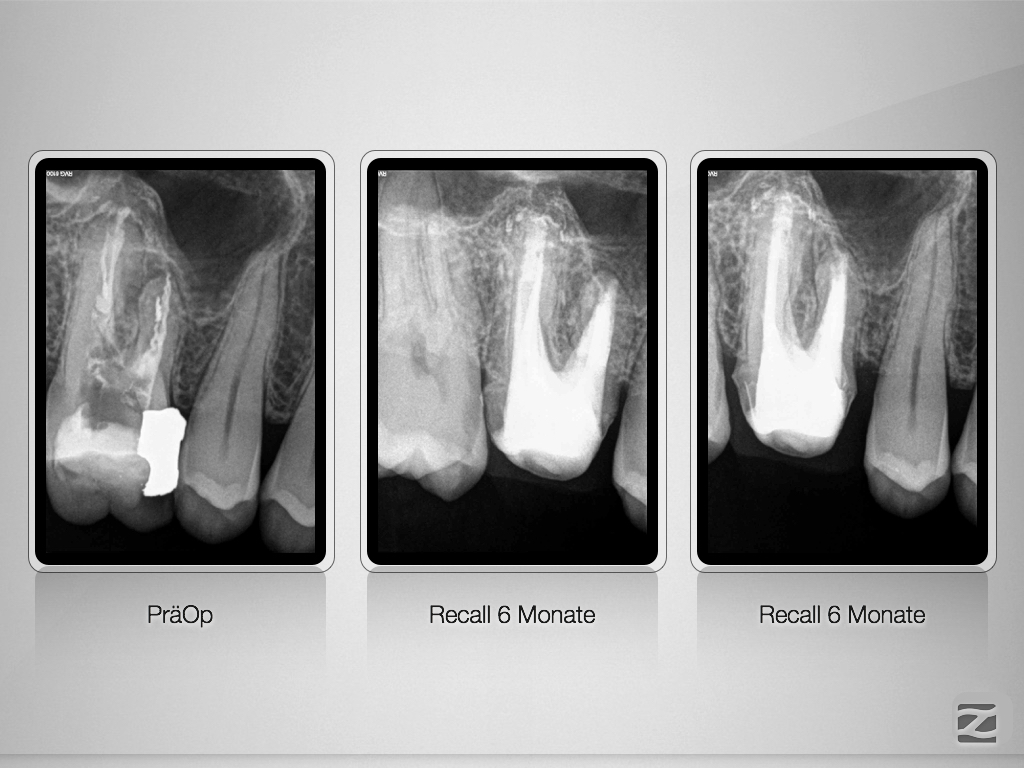

16D.012

Multiple Fragmente